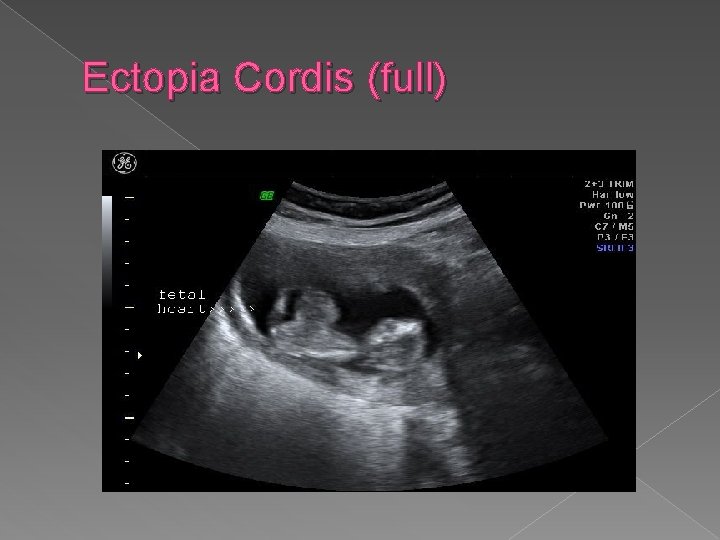

Ectopia Cordis In ectopia cordis, all or part of heart is located outside of chest cavity. It is frequently associated with intra-cardiac anomalies and omphalocele in Pentalogy of Cantrell. Sonographic Findings: � Small thorax � Extension of soft tissue outside thoracic cavity in which cardiac activity is noted.

Ectopia Cordis (full)